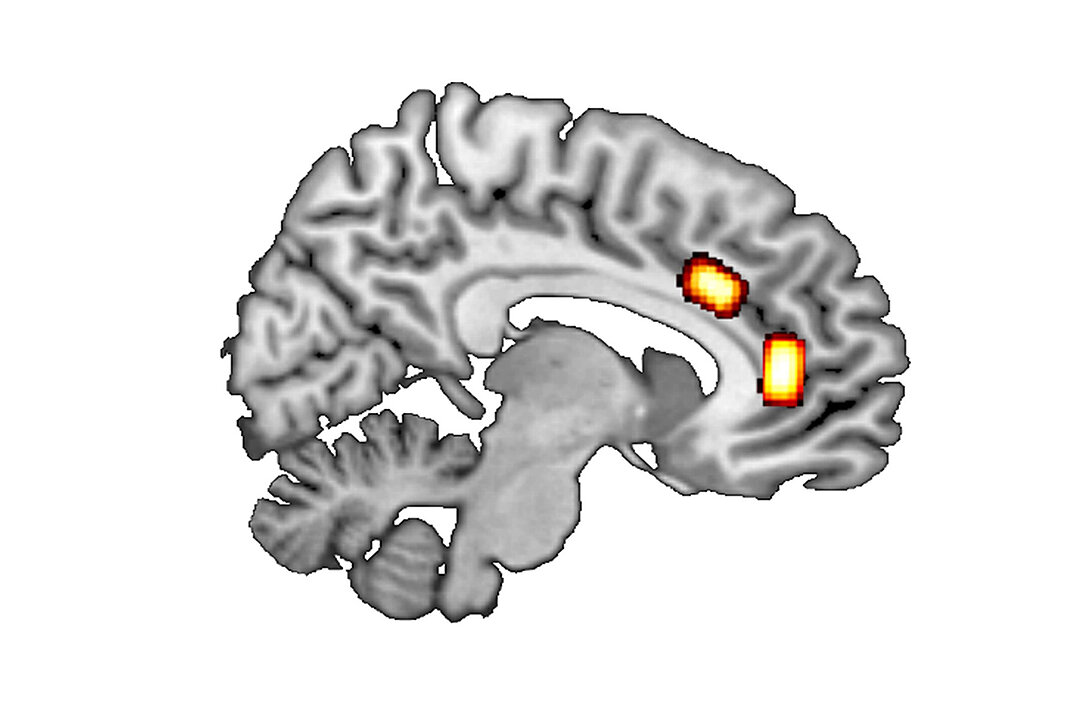

Longitudinal section of the brain: GABA/glutamate concentrations were measured at the locations marked (top: dorsal anterior cingulate cortex; further forward/bottom: ventromedial prefrontal cortex). (Photo: HHU / Luca Franziska Kaiser)

First, the researchers looked at so called ‘reward-based decisions’, which involve maximising reward by selecting the better of two options currently available. Luca Kaiser gives a simple example: “Where do I buy coffee on my way to work, depending on the price, quality and whether or not the café is on my way?” Previous results suggest that such decision-making processes in the brain are mainly processed in the ventromedial prefrontal cortex (vmPFC).

Unlike these reward-based decisions, ‘patch-leaving decisions’ are about long-term strategic considerations that include a careful balancing of immediate cost against (long-term) gain. An example of such a decision would be whether to move from Düsseldorf to Munich for a job offer. Prof. Jocham explains: “The job in Munich may offer a higher salary and a more interesting role, but may also involve stress and the effort involved in finding a place to live and moving to Munich – as well as higher rents and the loss of social contacts in Düsseldorf.” Thus, there are many factors that influence this type of decision. According to the literature, such decisions are made in the brain’s dorsal anterior cingulate cortex (dACC).

The two messenger substances glutamate and GABA may play a key role. The ratio between them, the so-called E/I balance, indexes the balance between excitatory and inhibitory neural transmission. The researchers used magnetic resonance spectroscopy to measure the concentrations of GABA and glutamate in different cortical areas of human volunteers.